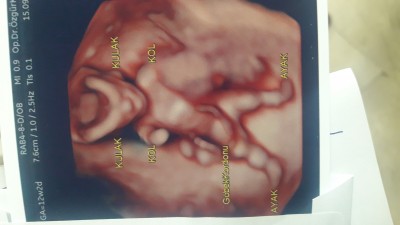

Ense kalinligimiz normal dedi ikili testimizi verdik &80 kiz dedi doktorumuz

image